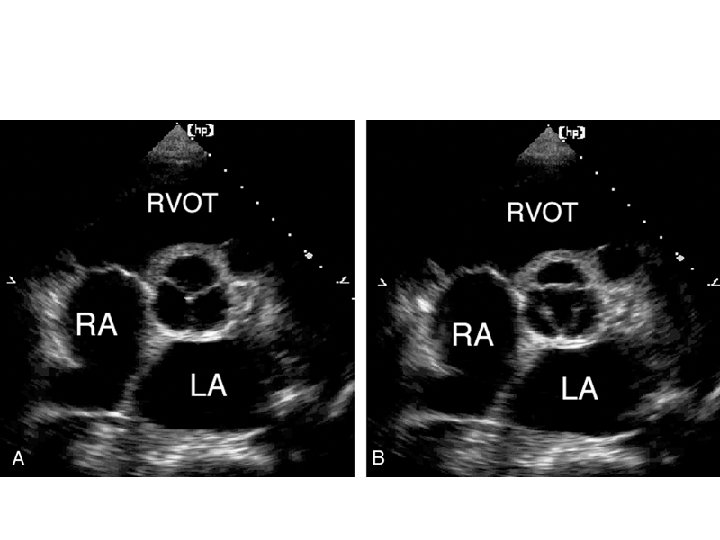

PARASTERNAL SHORT AXIS - AT PULMONARY ARTERY BIFURCATION LEVEL